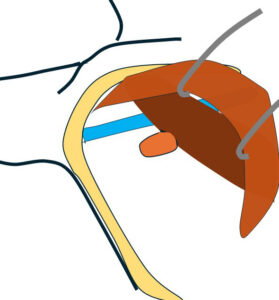

大胸筋(茶色)の裏に小胸筋(こげ茶色)

大胸筋の外側にリンパ節2つ、大胸筋の裏にリンパ節1個 これら3個がレベルⅠ

小胸筋裏にリンパ節(これが最大で2㎝)これがレベルⅡ

それより内側(奥)に比較的小さいリンパ節2個 これらがレベルⅢ

色分けすると 赤とオレンジ:レベルⅠ、 黄色:レベルⅡ 、赤(周囲に点線の小さいもの):レベルⅢ